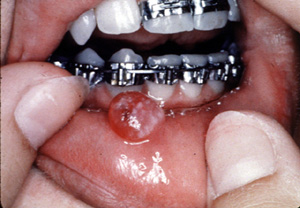

Aquí hay un ejemplo típico de  granuloma piógeno vascular, focalmente ulcerado. Éstos son generalmente asociados con algún tipo de irritación local; en este caso es probablemente el aparato ortodóntico. Por el color usted puede ver que la lesión es notablemente vascular y está casi exclusivamente compuesto de tejido de granulación.